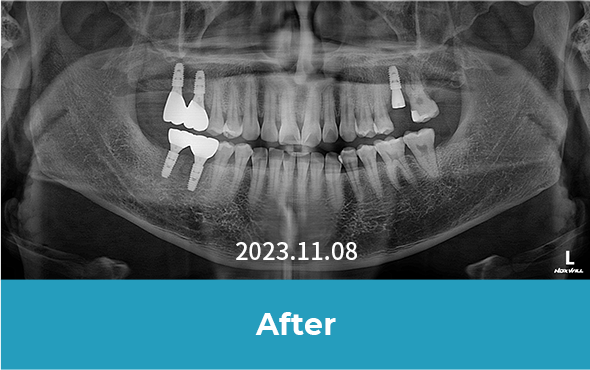

· 네비게이션 임플란트 / 임플란트 식립 2개월 후 보철물 체결 완료와 더불어 다량의 충치 크라운 치료 진행 case

• 치료 후 사진